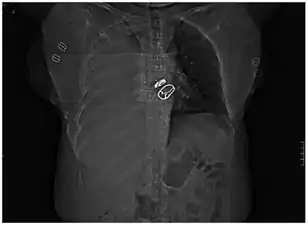

تصوير صدري بالرنين المغناطيسي يُظهر تدمي صدري في رضيعٍ عمره 16 يومًا